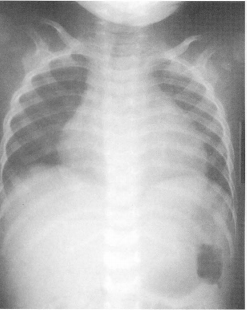

74. 8 個月大男嬰因為發燒、咳嗽 3 天來診,過去有白血球過低病史,本次檢查,白血球計 數 7,200/mm

3

,胸部 X 光如附圖,理學檢查心音較遙遠小聲,肝臟腫大,生命徵象為: 心搏每分鐘 174 次、呼吸 28 次、血壓 65/45 毫米汞柱、體溫 39.1°C。下列敘述何者正確?

(A) 應該作心臟超音波,如果有積水,要作心包膜穿刺引流 (B) 有病毒性肺炎 (C) 抗生素是不可或缺的治療 (D) 應該開始 dopamine 靜脈滴注